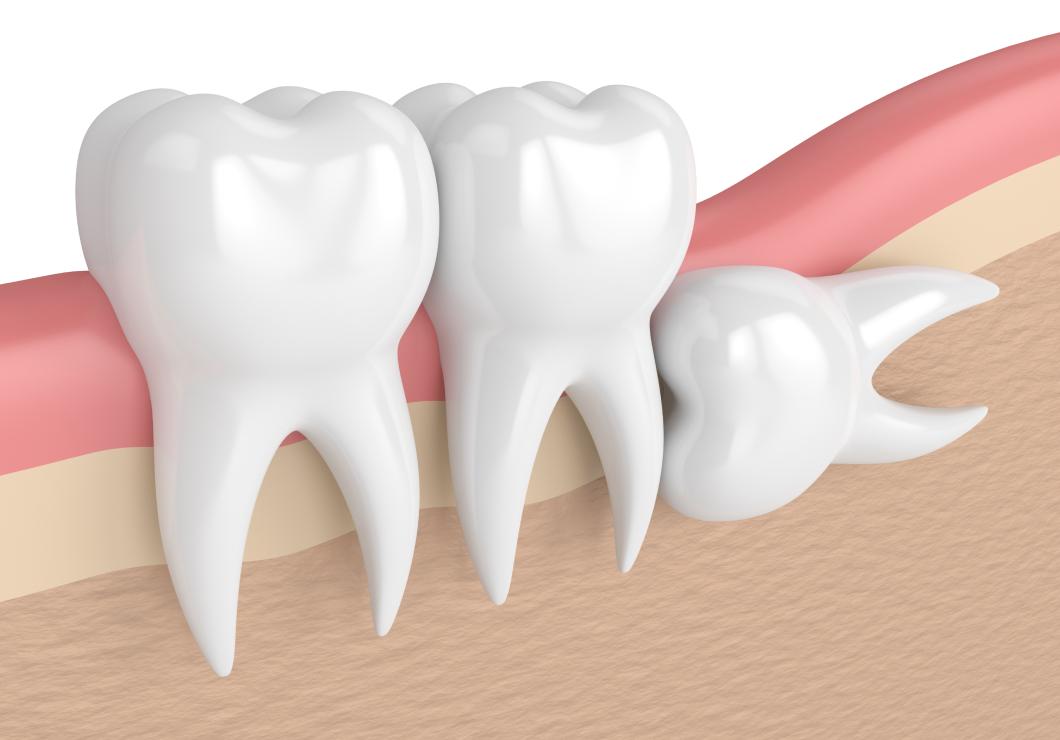

親知らずは、永久歯の中でも最後に生えてくる奥歯です。一般的に永久歯は15歳前後で生えそろいますが、親知らずは10代後半から20代前半にかけて生えてくることが多い歯です。

親知らずが横向きや斜めに生えてしまうと、歯と歯の間にすき間ができ、炎症や強い痛み、膿が出ることがあります。症状が悪化する前に、早めの受診をおすすめします。なお、当院での親知らずの抜歯は、外部から招いた専門性の高い歯科医師が担当いたします。